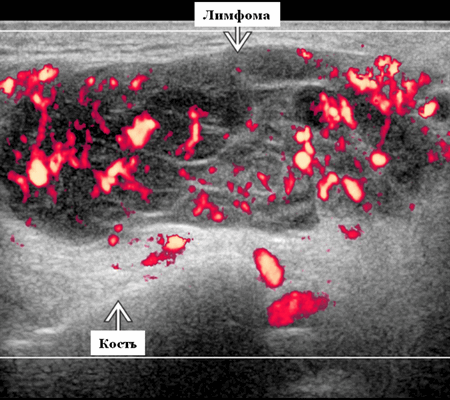

Цветной допплер. Узловая НХЛ. Выраженная центральная или внутриузловая гиперваскуляризация. Паренхима при неходжкинской лимфоме более диффузная железистая гиперваскуляризация. Васкуляризация от умеренной до выраженной в плохо очерченных образованиях.

- Узловая неходжкинская лимфома (НХЛ): одиночные или множественные увеличенные яйцевидные внутрипаротидные лимфатические узлы, которые на УЗИ гомогенно гипоэхогенны по отношению к паренхиме околоушной железы, эхо-картина сетчатая. Заднее акустическое усиление. Выраженная внутриузловая гиперваскуляризация

Лучший диагностический признак на УЗИ при узловой НХЛ: множественные однородные, четко выраженные образования околоушных желез и лимфаденопатия верхних отделов шеи. Паренхиматозная НХЛ: инфильтративная околоушная опухоль, фон СШ, BLEL

Серошкальное УЗИ. Узловая НХЛ. Одиночные или множественные увеличенные яйцевидные внутрипаротидные лимфатические узлы. Гомогенно гипоэхогенный по отношению к паренхиме околоушной железы. Сетчатый эхосигнал. Заднее акустическое усиление. Первичная паренхиматозная НХЛ. Рассеянный, неоднородный эхосигнал; нечеткие, гипоэхогенные, похожие на опухоль участки. В пунктате внутрикистозная или паренхиматозная кальцификация из-за конечной стадии воспалительного изменения. Небольшие кистозные области образуются из-за сдавления терминальных протоков лимфоидной гипертрофией. Множественные небольшие гипоэхогенные участки (представляют собой лимфоидные агрегаты), разбросанные на фоне ткани слюнной железы. Изменения могут имитировать хронический сиалоаденит и диагноз часто ставится при биопсии. На УЗИ необходимо искать аналогичное поражение других слюнных и слезных желез, фон синдром Шегрена, BLEL. Может иметь или не иметь перипаротидную и шейную лимфаденопатию